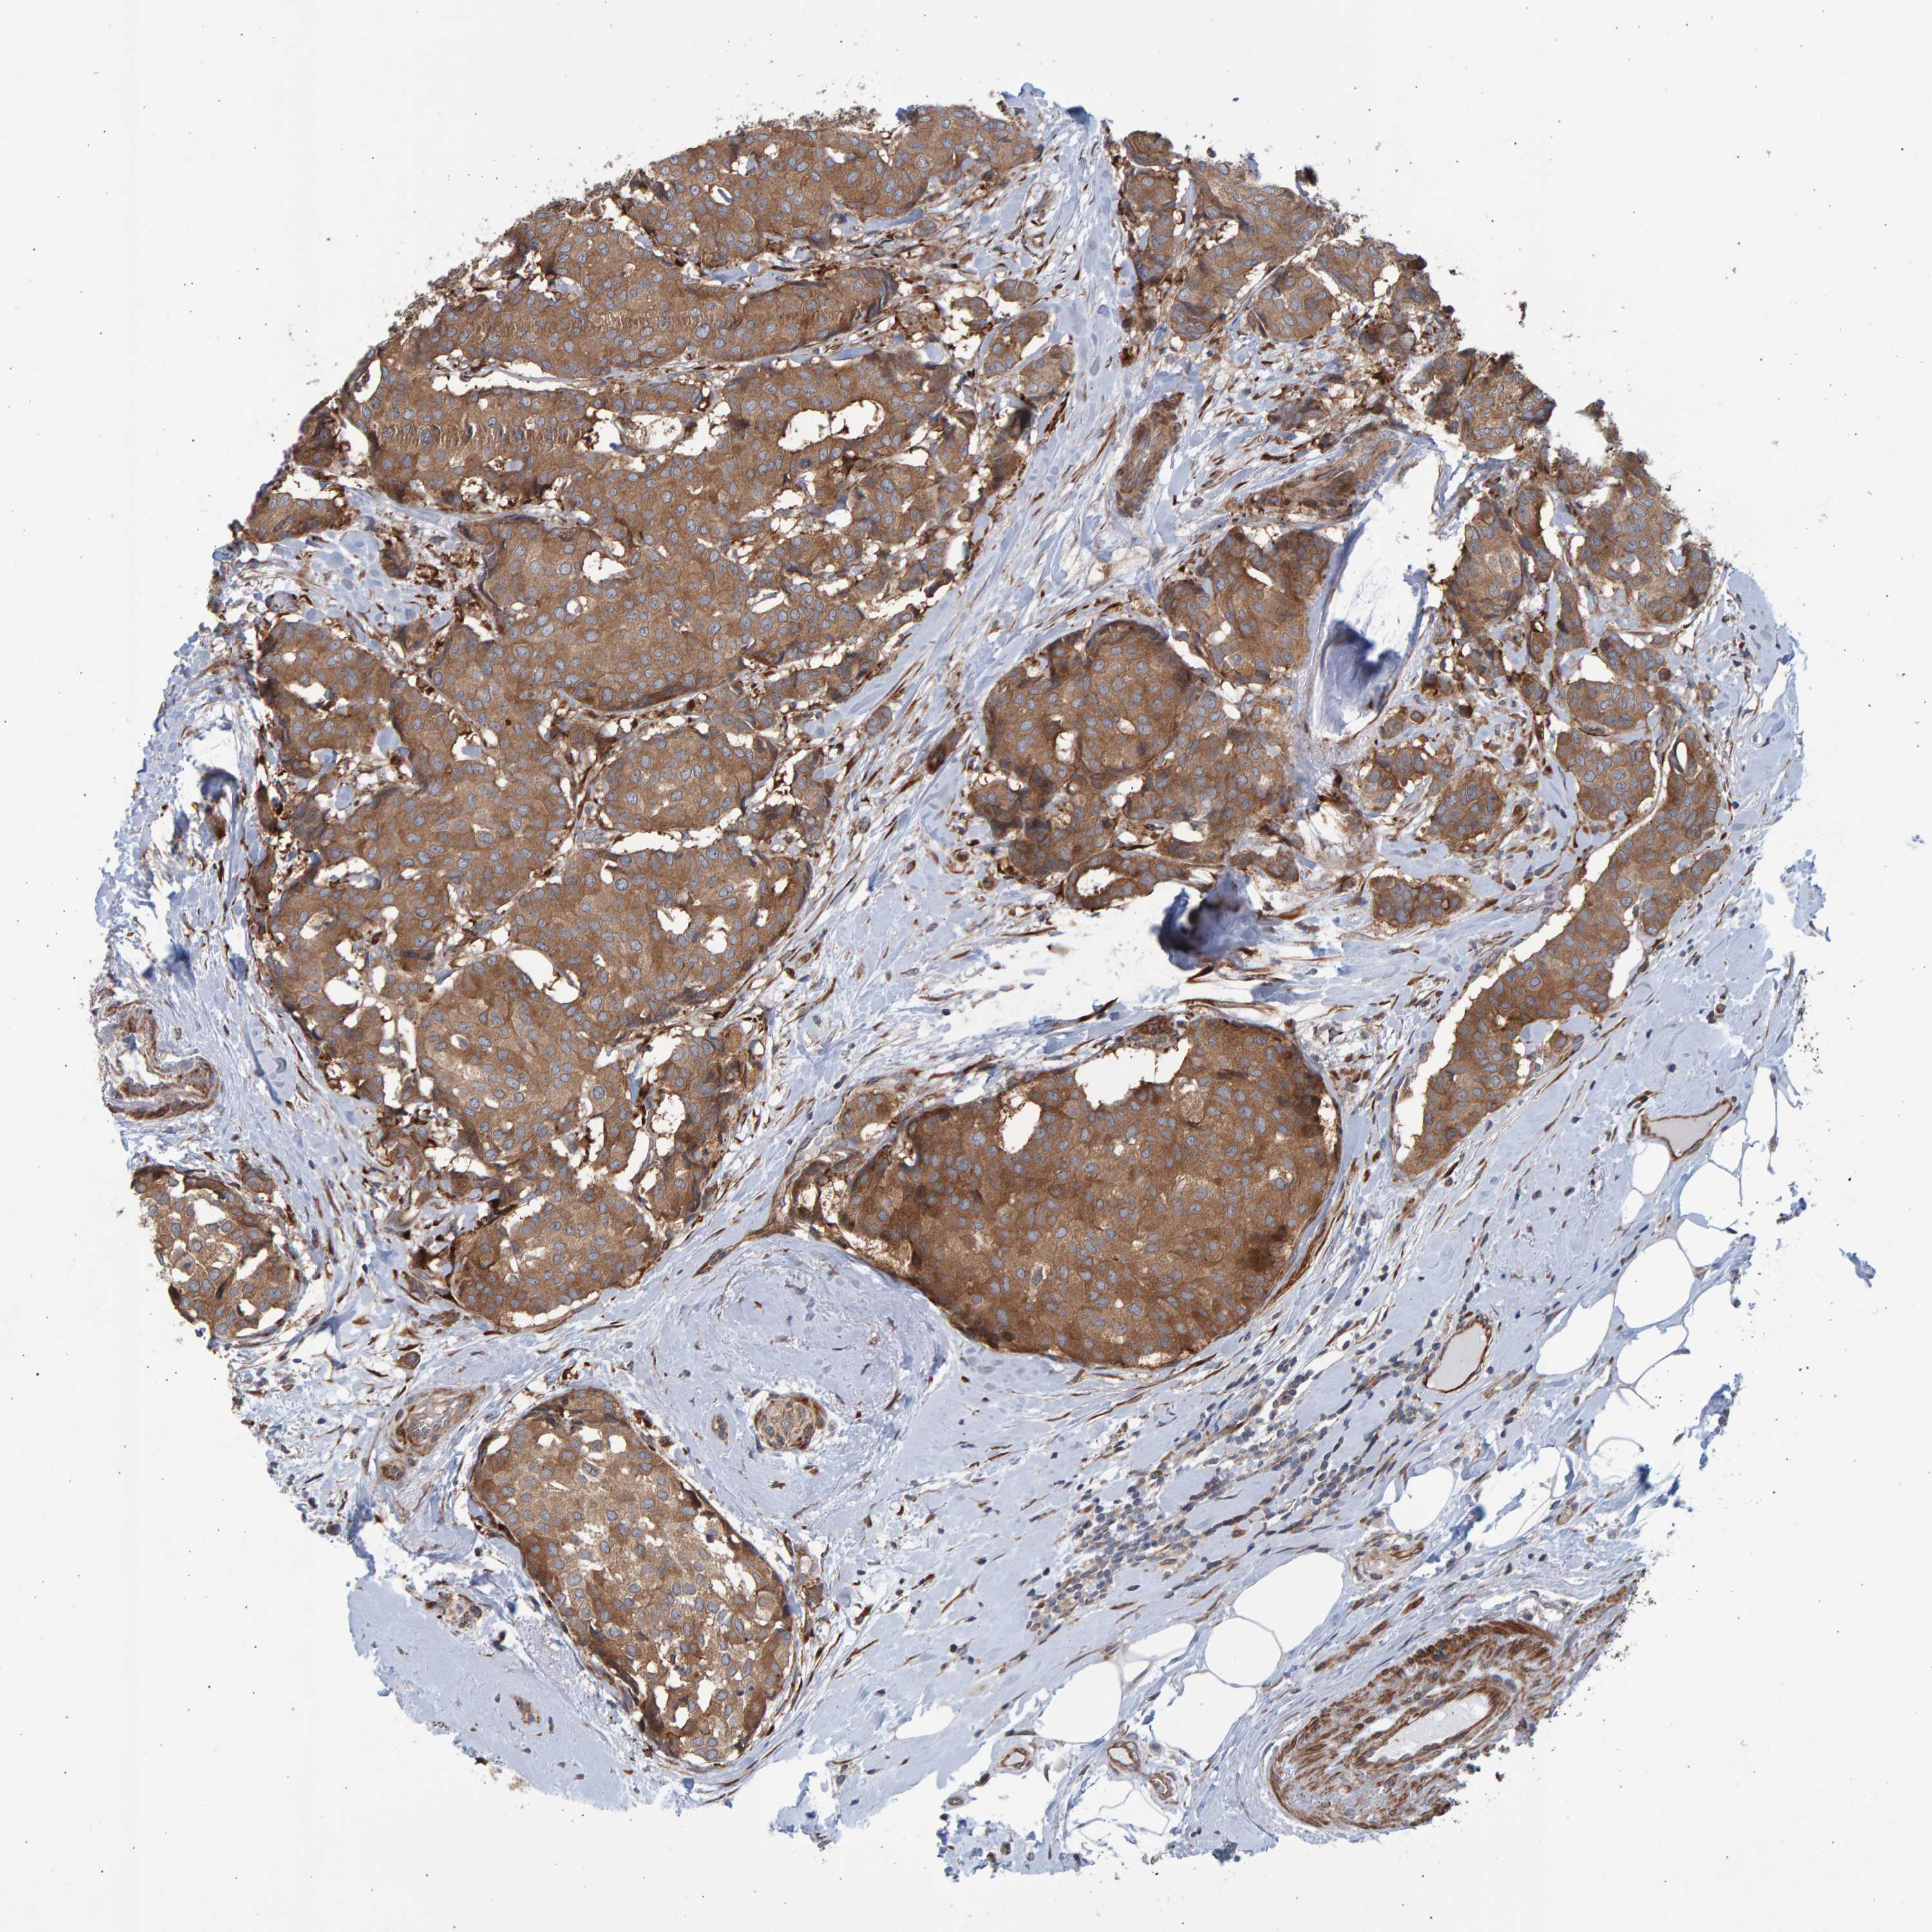

CANCER BREAST CANCER Show tissue menu

BRCA TCGA BRCA VALIDATION PROTEIN EXPRESSION